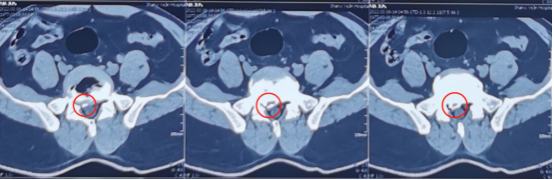

术前影像学资料

陕西冶金医院神经脊柱科的张少华主任、熊东主任接诊后,为小孙进行了详细的查体,并结合各项检查结果和影像学片子,发现他在腰5/骶1节段出现了比较严重的腰椎间盘突出,并造成较为严重的神经受压。